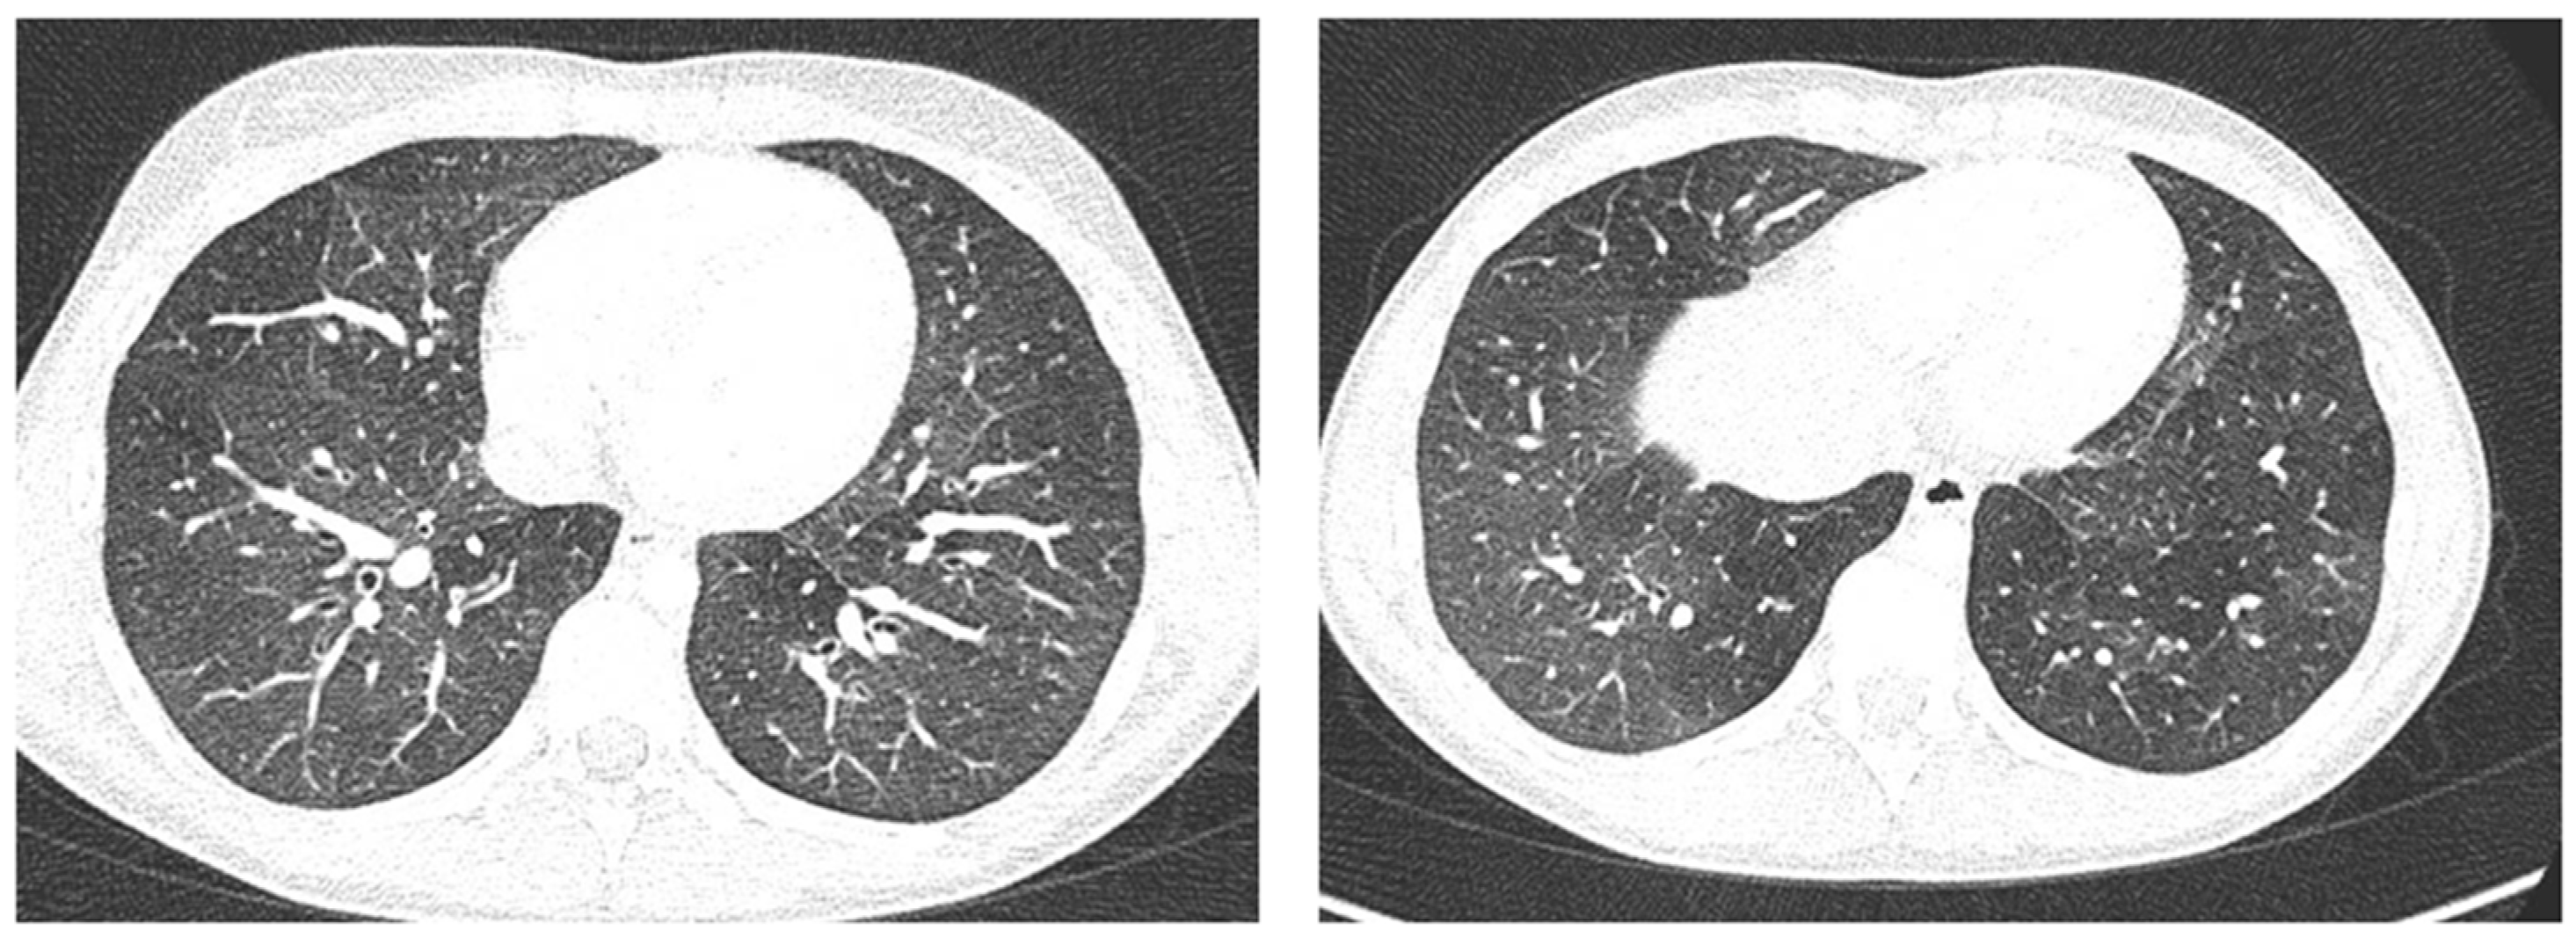

Case 6 was a 10-year-old girl with a medical history of allergic rhinoconjunctivitis recurring since childhood; her diagnosis of allergic asthma (T2-eosinophilic phenotype— “T2-high” [11,12]) was from 6 years of age. It has always been a severe phenotype despite adequate preventive therapy, so much as to require a progressive step-up of the therapy itself up to the maximum step [1,2,3]. Despite this, and the good adherence to therapy, she came to our attention at the pediatric allergy clinic of our hospital, reporting that she was still having recurrent symptoms, resorting daily to short-acting bronchodilators, and was also having nocturnal symptoms. She had an ACT of 20 points [13], and pathological control spirometry. Therefore, in consideration of the presence of severe eosinophilic T2 allergic asthma (T2-high), the patient was a candidate for the administration of a biological drug. However, before classifying the patient as such, a chest CT was performed to exclude the presence of other pathological respiratory conditions that could dissemble asthma (Figure 8).

Figure 8.

A representative coronal section from thoracic computed tomography (CT) scan reveals: thickening of the bronchial walls bilaterally, with filling of the bronchial lumen predominantly in the apical segment of the right upper lobe; picture of diffuse inhomogeneity of parenchymal density with diffuse and bilateral hypodense areas in relation to air trapping correlated to a picture of recurrent airway inflammation.

LUS was also performed, which showed a picture compatible with the features detected on CT (Figure 9).

Furthermore, evaluating some patients who had important ultrasound lesions (such as atelectasis of a certain entity, or diffuse sonographic interstitial syndrome), as in the first three cases, we wondered if some of these lesions may have already been present before the acute attack, and also in consideration of the finding of a positive ultrasound picture even in the stability phase, and after starting an adequate preventive therapy. Hence, there is a need to take into account the asthmatic phenotype and its severity for all patients, and also to evaluate the ultrasound patterns of patients in the stability phase in an outpatient setting, as in case 6. In the latter case—a patient with allergic asthma severe eosinophilic atopic type 2, but in a stability phase—the chest CT (Figure 8) showed signs of airway and lung parenchyma remodeling compatible with the patient’s severe clinical picture. LUS (Figure 9) showed a picture of diffuse short vertical artifacts, long confluent and non-confluent artifacts, and irregularities of the pleural line and sub-centimeter consolidations: lesions that, in the absence of acute respiratory pathology (as in our case), could be compatible with the remodeling pattern found on the chest CT.